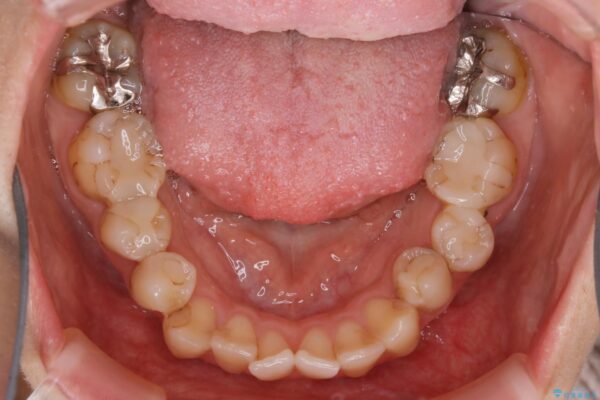

20代 女性 非抜歯で歯列をコンパクトに

前歯のガタつき、噛み合わせの不調を改善したいとご来院されました。

目立たない装置で矯正したいと希望されたため、インビザライン(マウスピース矯正)による非抜歯矯正を行いました。矯正を始める前に、虫歯などがあれば、先にすべて治療して全体のお口の状態を整えます。

治療前